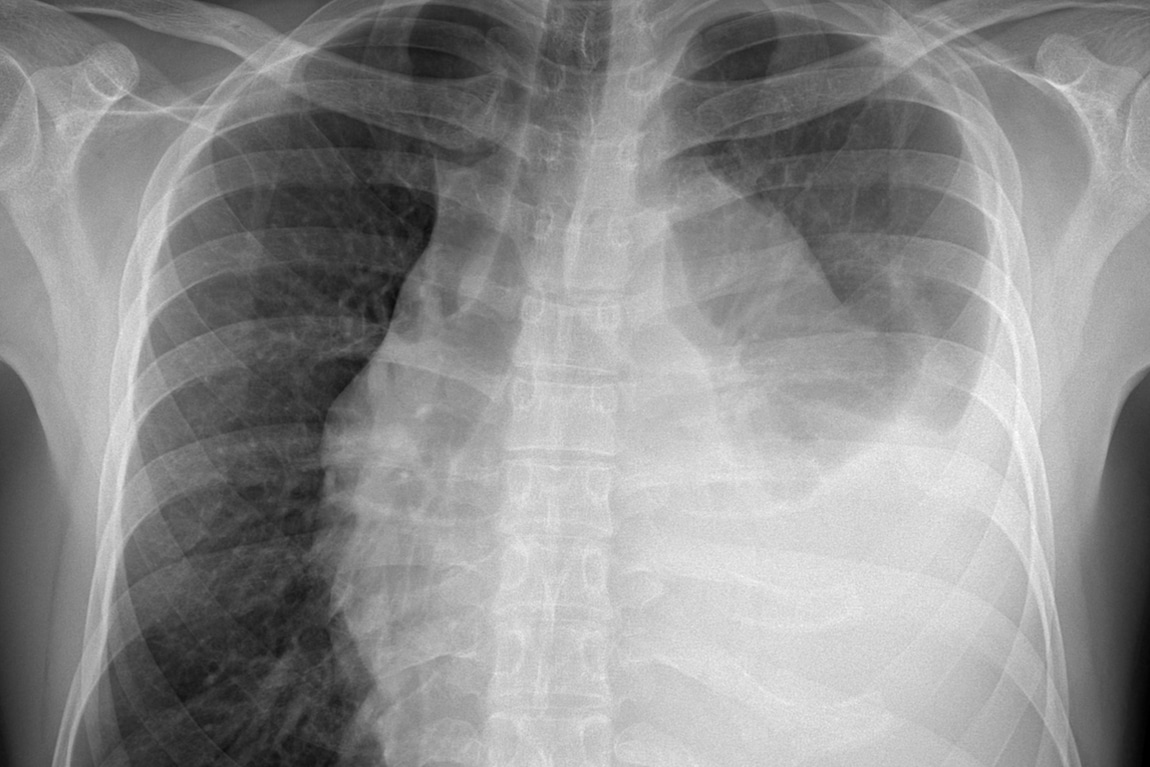

A collapsed lung, also known as pneumothorax, happens when air gets into the chest cavity and creates pressure on the lung. There are several different diseases and conditions that can cause this phenomenon, but collapsed lungs from car accidents usually result from blunt force trauma. The torso may hit the steering column, dashboard or doors, causing internal injury. Sometimes, fractured ribs or objects can puncture the lung, causing the lung to collapse.

Collapsed lung symptoms include chest pain on only one side, especially when taking a breath. You may experience elevated breathing and heart rate, a cough, fatigue, shortness or breath. Your skin may appear blue, from lack of oxygen in the bloodstream.